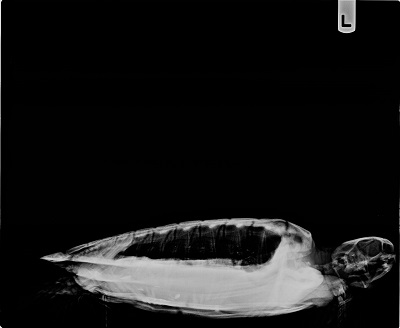

5.1 lb non-FP juvenile green

Minor abrasions on both plastron and carapace

In-house PCV = 32%, TP = 3.6 g/dl, glucose = 95, started on Ceftazidime, Vit B Complex, Normosol